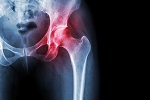

Regenerative Cell Injections vs. PRP: Which Is Right for Your Hip Pain?

Persistent hip pain can be a major setback, sidelining you from your sport and disrupting your life. While surgery is an option for some, many athletes are turning to advanced regenerative therapies like Platelet-Rich Plasma (PRP) and regenerative cell injections. Both treatments harness the body's natural ability to heal, but they work in fundamentally different ways. Understanding these differences is key to choosing the right path for your recovery and getting you back in the game.